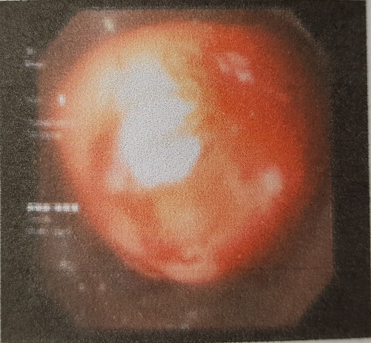

tháo lồng, bệnh nhân được chỉ định nội soi đại tràng kiểm tra và cắt u. Trên

màn hình nội soi quan sát thấy khối u có kích thước lớn bất thường, chiếm toàn

bộ lòng manh tràng, không nhìn thấy cuống u, việc cắt bỏ u qua đường nội soi đại

tràng trở nên không khả thi, các bác sĩ nội soi tiêu hóa đã hội chẩn với bác sĩ

Ngoại và quyết định chuyển Khoa Ngoại Tổng hợp để phẫu thuật cắt u.

Hình

2: Khối u manh tràng quan sát thấy trên màn hình nội soi đại tràng, kích thước

lớn choán chỗ toàn bộ lòng manh tràng